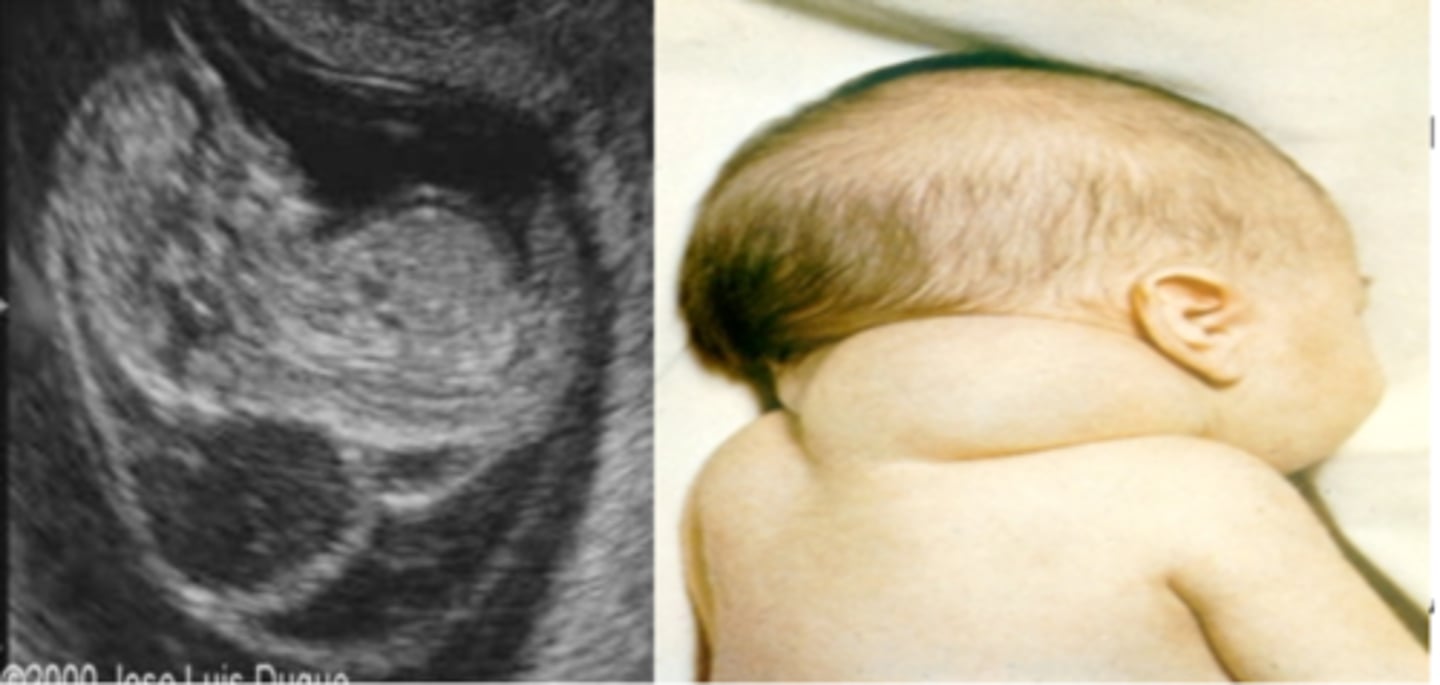

What is a cystic hygroma?

Large fluid-filled swellings involving jugular lymph sacs that fail to connect to lymphatic vessels.